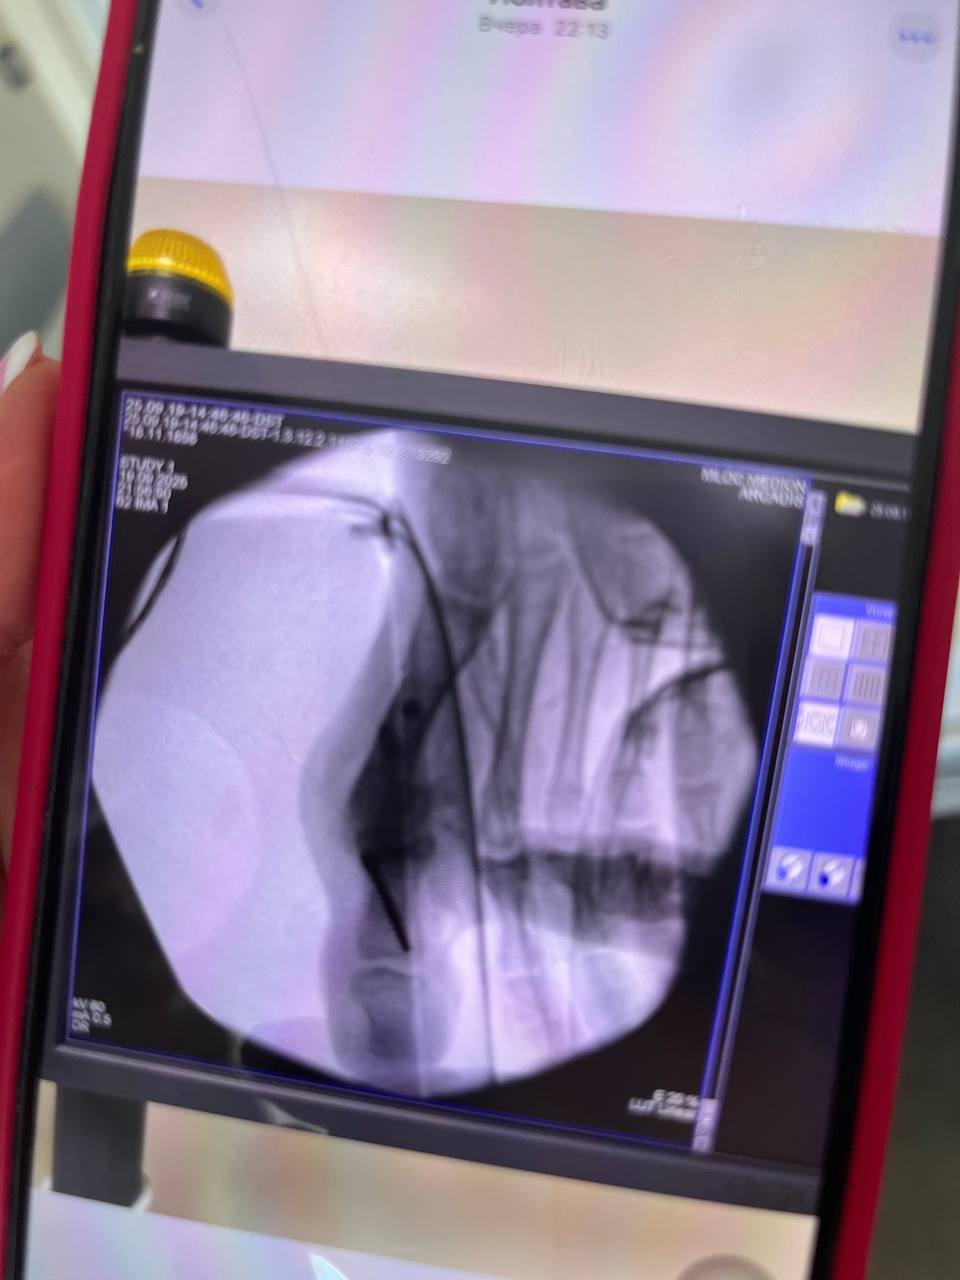

And now, one of her dreams has come true thanks to the help of the Bonum Ukraine Charitable Foundation and caring people who helped raise the necessary funds for implants. Margarita successfully underwent surgery on her knee joints and big toes. It was necessary to correct the X-shaped shape of her legs, as well as the deformation of her feet and big toes, and to eliminate painful sensations.